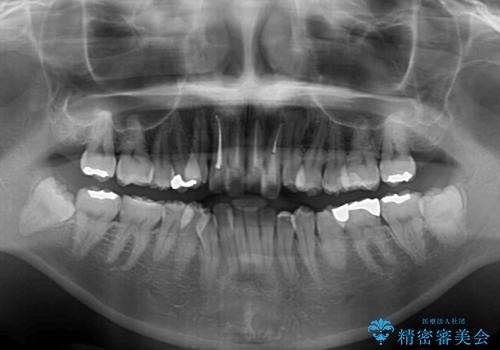

上顎前歯4本は、以前むし歯により神経をすべて取り除かれており、その影響で既に変色を起こしている状態でした。

4本とも歯根部先端の骨が炎症により吸収していることがレントゲン写真から示唆されたため、矯正治療後に4本を再根管治療し、その後上顎6歯をオールセラミッククラウンにて補綴治療することとしました。